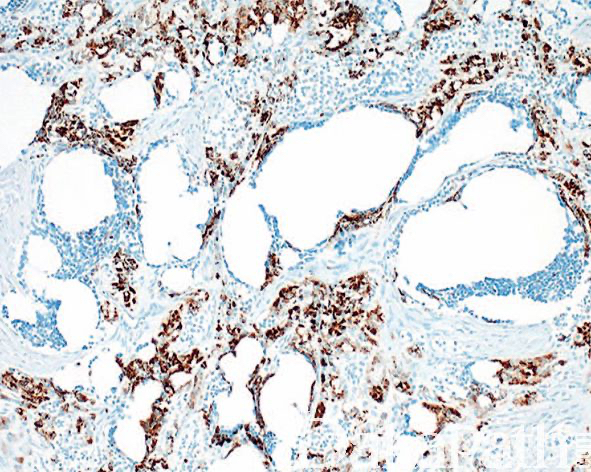

镜下主要可见 2 种细胞,神经母细胞样细胞和上皮性细胞;

神经母细胞样细胞为小的圆形或小立方,核深染、固缩状,多呈巢状或假腺泡状排列;有时该类细胞之间可见神经纤维网样物质;

上皮性细胞体积大,胞质含色素,核呈空泡状,核分裂像罕见,围绕巢状或假腺泡状结构周围;

细胞巢之间可见致密的纤维结缔组织,位于颅面部的肿瘤常可见到骨小梁浸润;

上皮性细胞表达 CK、EMA、HMB45. vimentin、NSE 和 Leu 7;小圆细胞表达 NSE 和 Leu 7,部分病例表达 SYN、GFAP 和 S-100,罕见表达 NFP 和 CD99。